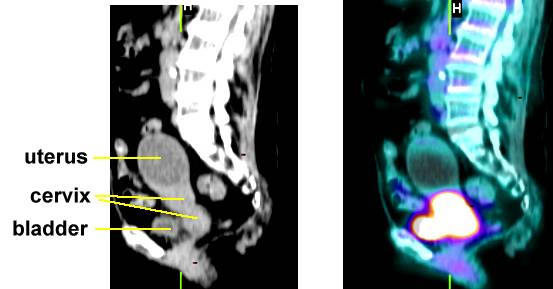

f , Stage IIIb bulky cervix cancer here and here., early stage cervix (IB2) PET here also PET scan uterus here and here and here. PET scan of ovary cancer here. PET scans are good for looking at lymph node spread: go here and here PET scan of vulva cancer that has spread to the right groin lymph nodes is noted below |